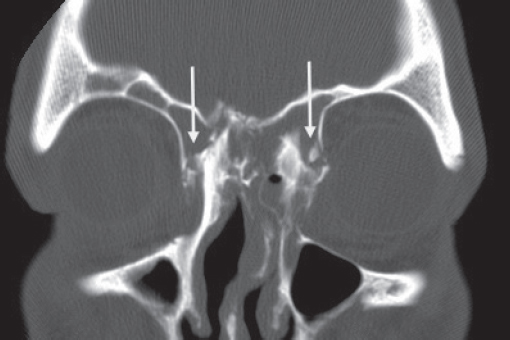

Historically, plain sinus X-rays were used to evaluate facial fractures. Thin cut (1–1.5 mm) axial computed tomography (CT) scans are now the gold standard for diagnosis of frontal sinus fractures. These images are readily reformatted into coronal, sagittal, and threedimensional (3D) reconstructions to improve the diagnostic accuracy. Axial cuts provide excellent information about the anterior and posterior table as well as pneumocephalus ( Fig. 63.5 ). Coronal reconstructions demonstrate the frontal sinus floor, orbital roof, and frontal recess ( Fig. 63.6 ). Sagittal views can assist with evaluation of frontal recess and skull base injuries ( Fig. 63.7 ). Threedimensional reconstructions can be very helpful in delineating the location of bone fragments and reducing the need for excessive dissection intraoperatively ( Fig. 63.8 ). Access to the PACS ( p icture a rchiving and c ommunication s ystem) or some type of presurgical planning software allows the surgeon to manipulate the reconstructions in space, gaining a greater understanding of depth and spatial relationships of the injury ( Video 63.1).